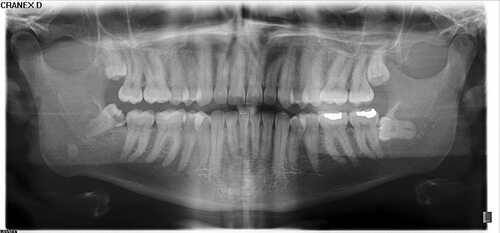

Фото кисты зуба мудрости

В данной статье представлены разные фотографии кисты зуба мудрости, чтобы вы могли просмотреть ее визуальное представление. Просмотр фотографий поможет вам лучше понять, как выглядит киста зуба мудрости и какие изменения она может вызывать в полости рта.